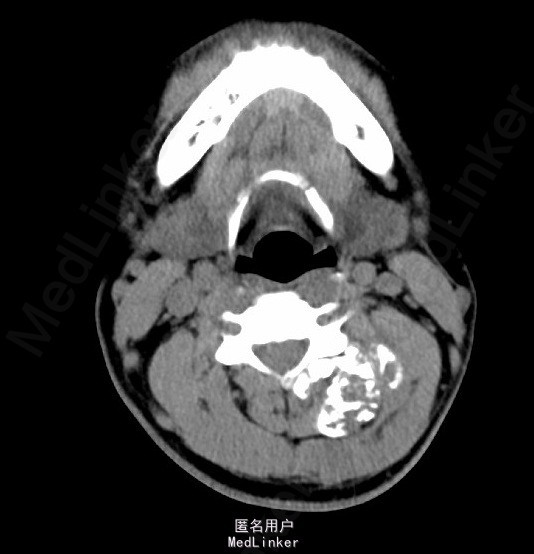

辅助检查:颈椎正侧位片示:颈部左后份软组织内见多发片状稍高密度影,约C2、3椎体平面,与椎体附件结构分界不清,颈部MRI检查示:左颈后肌间隙肿块,大小约4.9*3.9*5.4cm,考虑肿瘤病变可能性大,其他待排。入院后积极完善相关检查,查CT示:约颈3-4平面左侧软组织内见类圆形混杂密度肿块影,最大截面约4.6x4.5 cm,内见多发不规则钙化灶,增强扫描见不均匀强化,局部与邻近附件骨质关系密切,局部皮质稍显毛糙,上述考虑肿瘤性病变可能